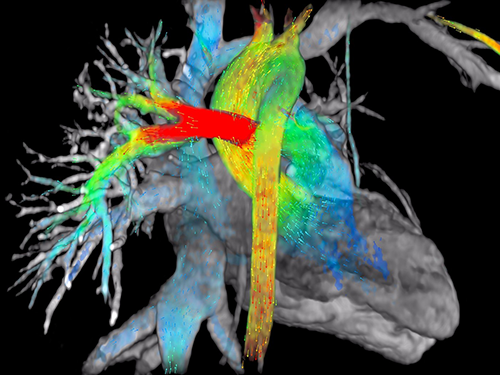

Programas de estudio

Adaptados a los tiempos modernos en los que las plataformas tecnológicas son una herraienta esencial.